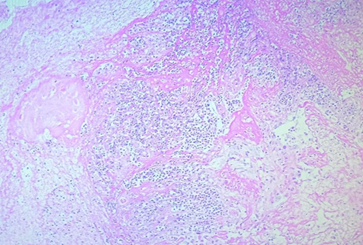

Патологоанатомическое исследование подтвердило наличие острого гнойного среднего отита с остеомиелитом височной кости, отогенного сепсиса, инфекционно‑токсического шока, выраженного поражения лёгких по типу острого респираторного дистресс-синдрома (ОРДС) (рис. 1) и тромботических изменений в матке (рис. 2) и других органах.

Рис. 1. Микроскопический препарат легких (фото авторов)

На рисунке 1 представлены признаки острого респираторного дистресс-синдрома (ОРДС), двусторонняя пневмонией с интенсивной альвеолярной экссудацией и кровоизлияниями. Микроскопически наблюдаются множественные очаги утолщения легочной паренхимы, гиперплазия альвеолярных клеток II типа и тромбоз капилляров.